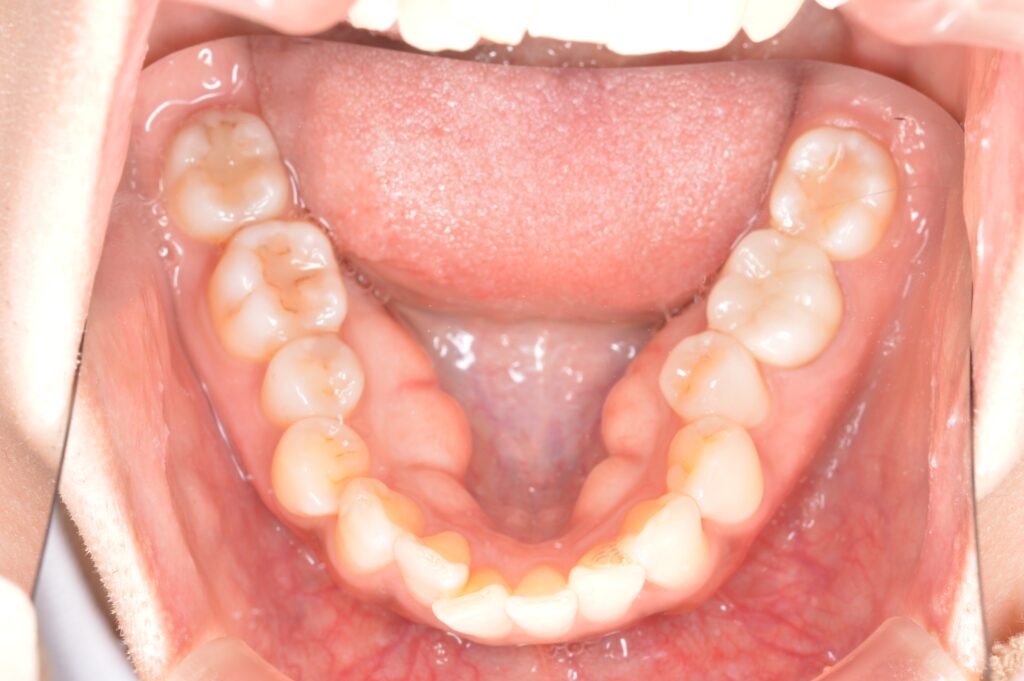

インビザライン(マウスピース矯正)にて上の前歯の重なりと下のデコボコを解消したケース

| 主訴 | 上の前歯が曲がって重なっている |

| 治療内容 | 上の前歯の重なりと、下のでこぼこの治療希望あり。インビザラインを用いて、矯正治療を行った。患者様はこちらの指示通り、確実にマウスピースを使用してくださった。微調整のため、追加アライナーの作成を2回行い、歯列が整ったので、保定に移行した。 |